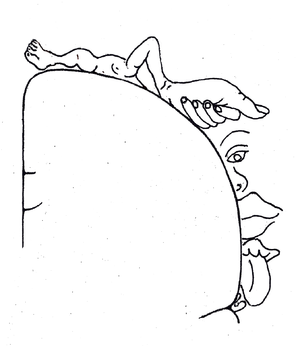

يسمى رسم خرائط أسطح الجسم في الدماغ التنظير الجسدي . في القشرة ، يشار إليها أيضًا باسم أنيسان القشرة . ومع ذلك ، فإن خريطة سطح الدماغ هذه ("القشرية") ليست ثابتة. يمكن أن تحدث التحولات الدرامية استجابةً للسكتة الدماغية أو الإصابة.

يشمل التلفيف خلف المركزي القشرة الحسية الجسدية الأولية ( مناطق برودمان 3 و 2 و 1) يشار إليها مجتمعة باسم S1.